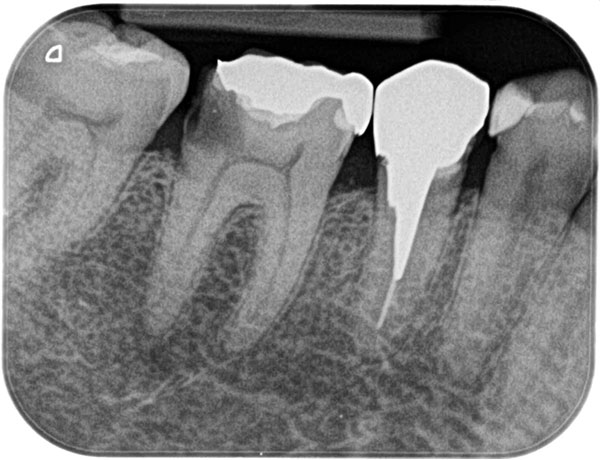

主訴: 噛むと痛い、奥歯が違和感ある

保険治療では発見することが難しい4つ目の神経を

歯を大きく削らずに見つけられます。